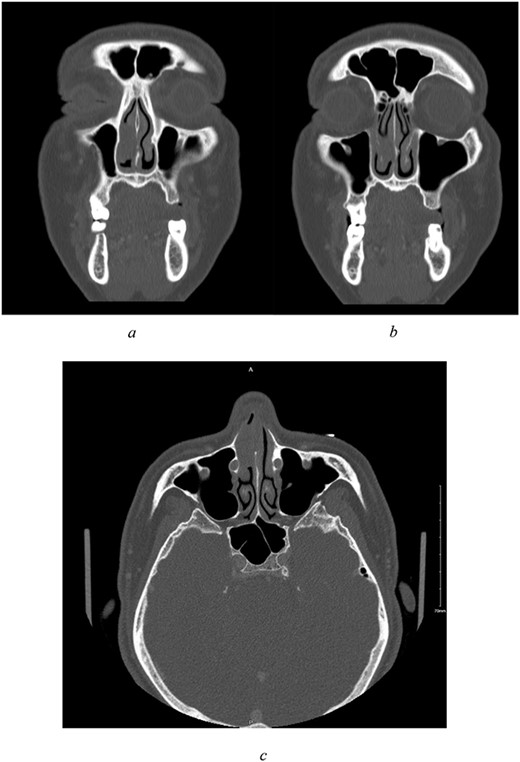

Sinus computed tomography (CT) (Fig. 1a–c) revealed mild mucosal hypertrophy of the inferior turbinates and a non-enhancing mass lesion attached to the cartilaginous part of the nasal septum causing partial obstruction. Nasal endoscopic examination was performed under general anaesthesia for mass excision and biopsy. The mass was smooth, pedunculated, and arising from the septum. Pathology results indicated a diagnosis of sinonasal low-grade n-ITAC, classified as pT1 NX.

(a–c) Preoperative CT scan of paranasal sinuses with contrast. All imaged paranasal sinuses appears clear with no significant mucosal thickening or air-fluid level detected. Intact bony boundaries of the paranasal sinuses. (a, b) Coronal cut, showing clear paranasal sinuses, intact bony boundaries, and a non-enhancing soft tissue mass in the right anterior nasal cavity with poor demarcation to right inferior turbinate, attached to the cartilaginous part of nasal septum. (c) Axial cut.